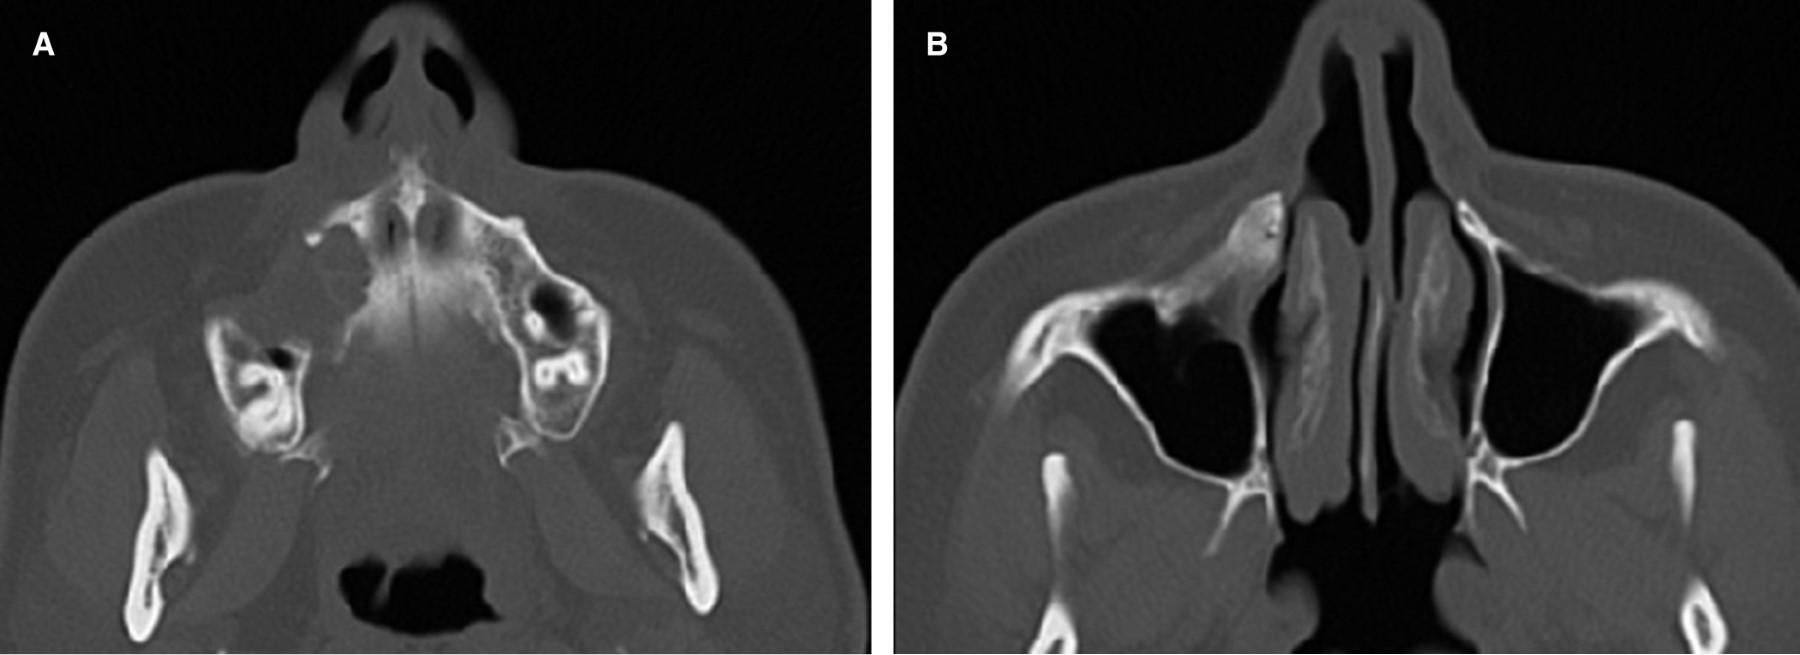

Se envía a estudio histopatológico, donde se confirma el diagnóstico de: granuloma central de células gigantes. Se obtiene una tomografía computarizada simple de control a un año, donde se aprecia una evolución favorable, no presenta datos de recidiva y se aprecia el hueso maxilar en franca recuperación. La paciente actualmente evoluciona de manera adecuada sin sintomatología asociada (Figura 4).

Figura 4